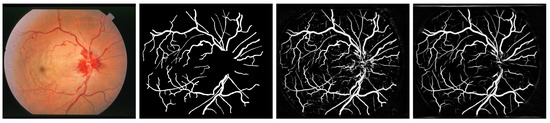

2. Methodology